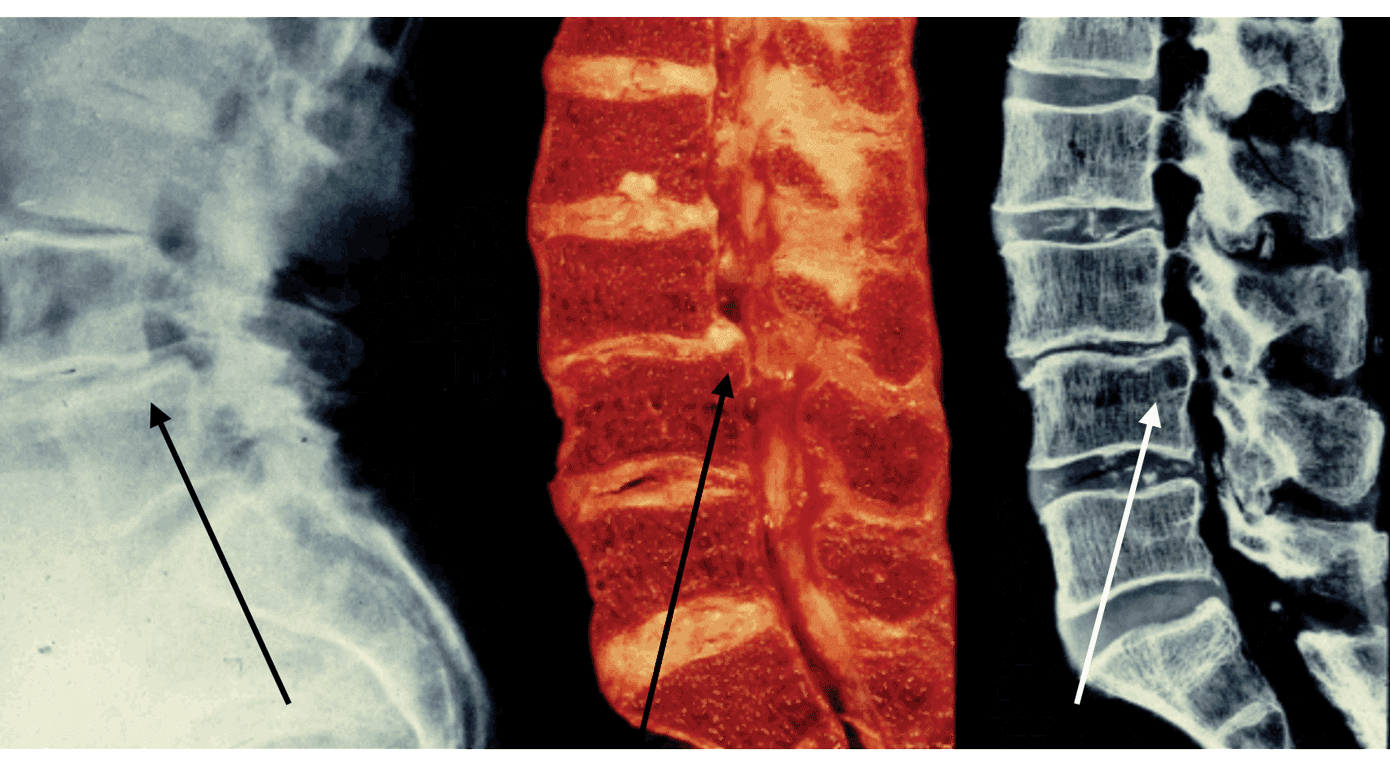

Ultimativt kan der ske en fuldstændig afglidning, hvor den øvre hvirvel ikke længere understøttes af den kaudale. Dette kaldes spondyloptose – i litteraturen også omtalt grad V. Istmisk arkolyse – en knogledefekt i pars interarticularis mellem facetled og hvirvel – leder oftest til svær fremadglidning. Istmisk arkolyse uden fremadglidning kan dog betegnes grad 0-SL (Figur 2A). Generelt er graden af SL associeret til sværhedsgraden af symptomerne [4].

Symptomgivende ISL ses primært hos børn og unge i teenageårene og kan skyldes talrige mikrotraumer i pars interarticularis forårsaget af stress efter gentagne lumbale ekstensioner f.eks. udløst af gymnastik eller kampsport (Figur 2B). Visse befolkningsgrupper, særligt grønlændere, er genetisk prædisponerede for udvikling af ISL, og ca. 30% af grønlænderne har ISL [7, 11]. Det er usandsynligt, at grønlændere har flere mikrotraumer end øvrige befolkningsgrupper, og derfor er en arvelig komponent med manglende ossifikation af pars interarticularis (arkolyse) plausibel. Columna er primært afficeret ved L5-S1-leddet. Symptomer ved ISL opstår typisk i to perioder – første gang i 5-7-årsalderen og anden gang i puberteten. Der er ved ISL modsat ved DSL en overrepræsentation af hankøn i forholdet 2:1, og prævalensen af ISL er 2,6-11,5%, svarende til 1-2 børn i hver skoleklasse. Blandt børn med bilateral spondylolyse (arkolyse) forekommer ISL i 40-66% af tilfældene [12, 13].